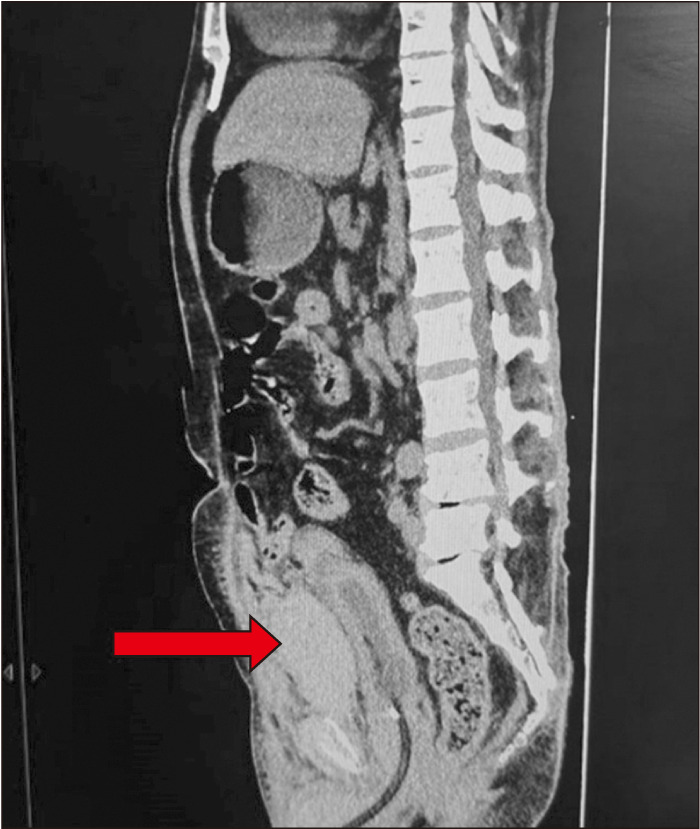

Pelvic hematoma post prostatic urethral lift: A need to be vigilant in high-risk patients.